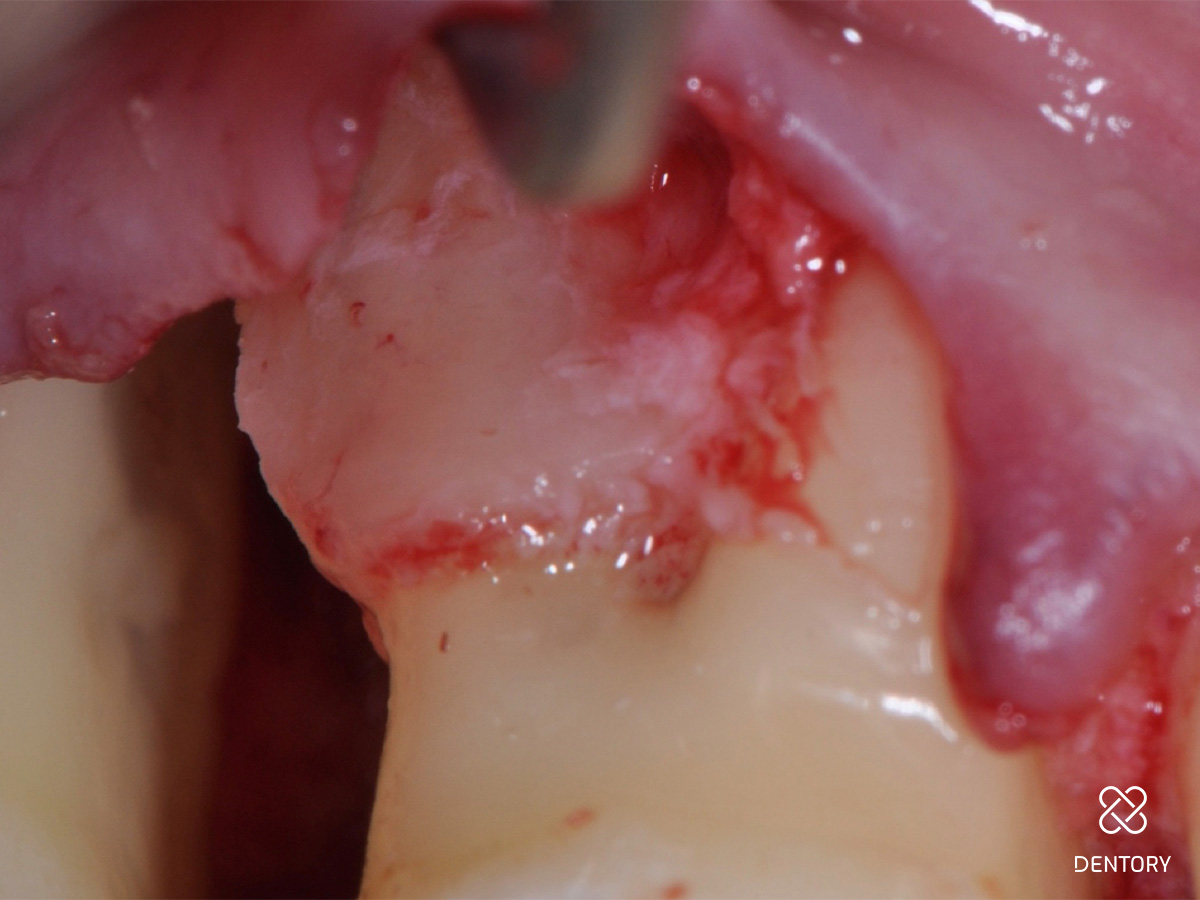

Abbildung 4

Lappenpräparation: Die Lappenpräparation beginnt mit der intrasulkulären Inzision auf den bukkalen Flächen der beiden zum Defekt benachbarten Zähne (16 und 17) mit einer mikrochirurgischen Skalpellklinge. Es werden keine vertikalen Entlastungen durchgeführt. Wenn der Zugang zum knöchernen Defekt nicht ausreicht, kann ein weiterer Nachbarzahn in die Lappenpräparation integriert werden.